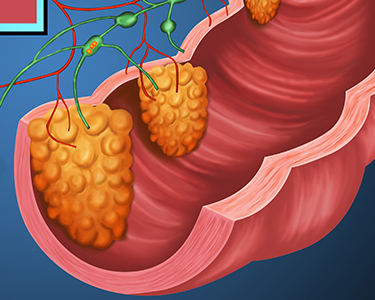

Our newest hemorrhoid treatment: Hemorrhoidal Banding

You’ve likely heard the term ‘hemorrhoid’ before, and probably know someone who has had them! In fact, about 50% of adults over the age…